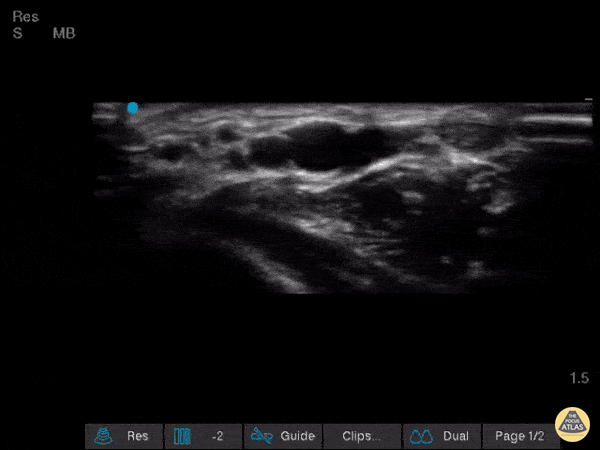

Vascular - Dual Radial Artery

Very interesting find while performing a wrist ultrasound where we see the presence of two radial arteries Image courtesy of Robert Jones DO, FACEP @RJonesSonoEM Director, Emergency Ultrasound; MetroHealth Medical Center; Professor, Case Western Reserve Medical School, Cleveland, OH View his original post here